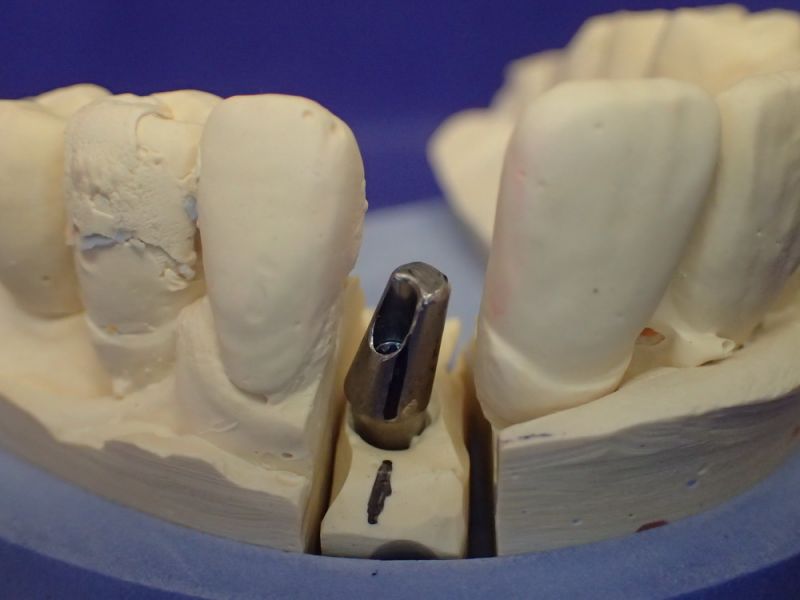

Kieler Patient erhält implantatgestützte Kronenversorgung 22

In diesem Fall wäre es sogar möglich gewesen auf das neue Implantat 22 zu verzichten und eine Versorgung auf den vorhandenen Implantaten zu begründen.

Das hätte aber zu einem wesentlich höheren wirtschaftlichen Aufwand geführt, weil die dann notwendige Prothetik, die von den Implantaten hätte entfernt und nachfolgend wieder neu hätte erstellt werden müssen, wesentlich teurer gekommen wäre, als ein neues Implantat mit einer neuen Krone darauf.